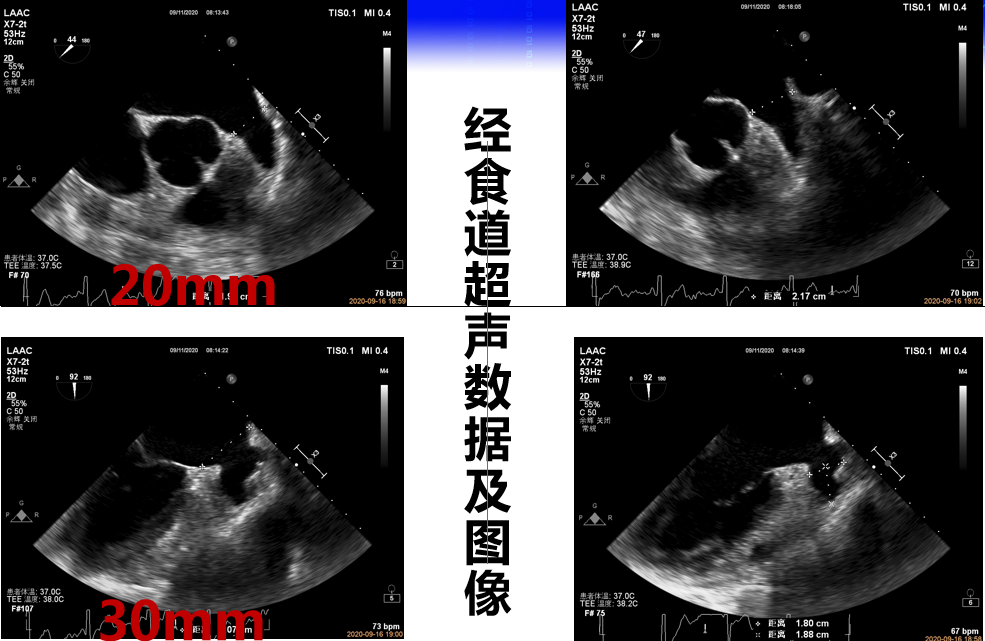

图4:多角度TEE下左心耳开口及深度直径(按塞式封堵伞方式测量)

图5:TEE测量固定盘着陆区尺寸20 mm,覆盖盘外口尺寸30 mm(盖式封堵伞测量)

拟选择24-26mm LACbes 盖式封堵伞。